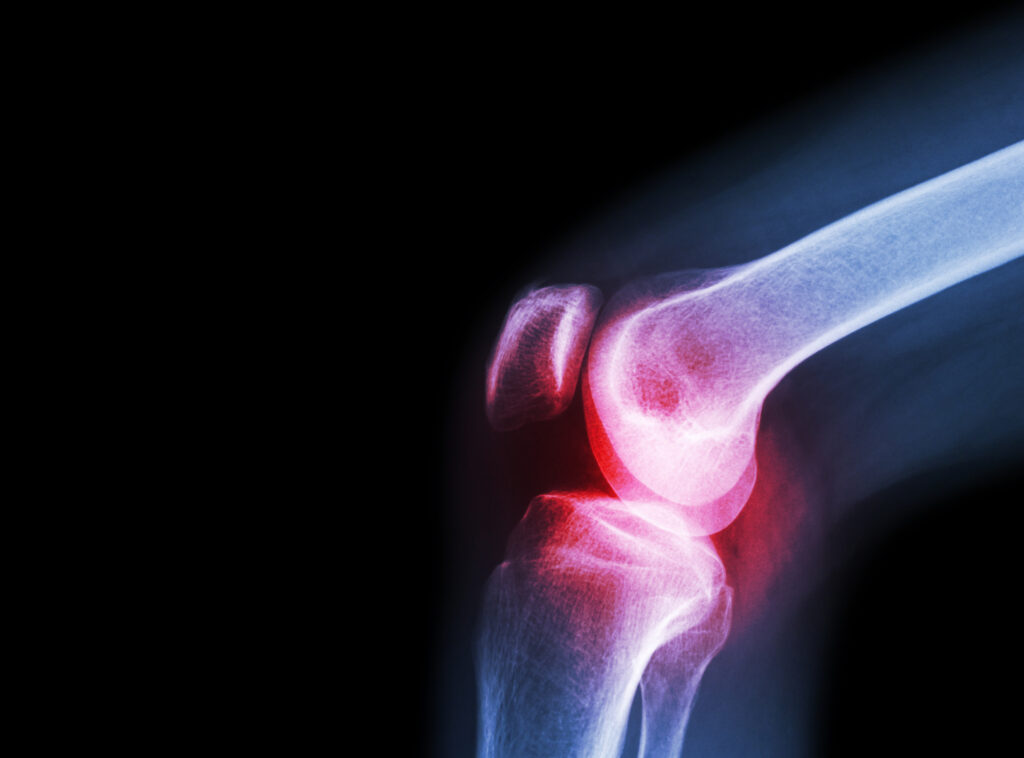

是的,患有风湿性疾病的人每当阴雨天气疼痛就会加剧。

为什么呢?因为中医学认为风湿是由风、寒、湿所造成的,也称之为痹症。《素问 痹论》:“风寒湿三气杂至,合而为痹也。其风气胜者为行痹,寒气胜者为痛痹,湿气胜者为着痹也。”所以当下雨天气时温度比较低、空气中湿度比较大且经常伴有狂风,患有风湿的患者疼痛就会加剧。